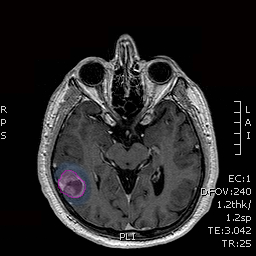

Διάγνωση Απαραίτητα είναι: Η λεπτομερής λήψη ιστορικού και η κλινική εξέταση, Η μαγνητική τομογραφία του εγκεφάλου με σκιαγραφικό, Σε ορισμένες περιπτώσεις: Η μαγνητική αγγειογραφία ή/και φλεβογραφία του εγκεφάλου, Η μαγνητική φασματοσκοπία, Η μαγνητική τομογραφία του εγκεφάλου με σκιαγραφικό για νευροπλοήγηση, Σε περίπτωση εξεργασίας/εξεργασιών με υποψία μεταστατικής προέλευσης επιπλέον ογκολογικός έλεγχος (απεικονίσεις άλλων οργάνων, καρκινικοί δείκτες κα) |